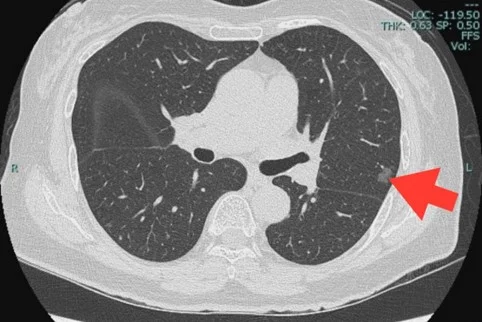

CT เพื่อประเมินรอยโรค

เมื่อตรวจพบความผิดปกติจากภาพ X-ray แล้ว ขั้นตอนต่อไปคือ การประเมินภาพถ่ายรังสีที่ละเอียดขึ้น การทำ X-ray คอมพิวเตอร์ (CT) ซึ่งจะสามารถประเมินลักษณะก้อนโดยละเอียด เป็นภาพตัดแบบสามมิติ ประเมินทั้งลักษณะก้อน ความเข้ม ขนาด การกดเบียดอวัยวะข้างเคียง เป็นต้น โดยหากพบก้อนจาก X-ray ปอดทั่วไปแล้ว จะแนะนำให้ทำ CT แบบฉีดสารทึบรังสี ใช้ปริมาณรังสีปกติของ X-ray คอมพิวเตอร์ ซึ่งจะสามารถจำแนกรายละเอียดของความผิดปกติได้ชัดเจนขึ้น แต่หากมีข้อจำกัดของการฉีดสารทึบรังสี เช่น การทำงานของไตบกพร่อง แพ้สารทึบรังสี เป็นต้น อาจใช้วิธีไม่ฉีดสารทึบรังสีได้เช่นกัน แต่รายละเอียดบางอย่างอาจไม่ชัดเจนเทียบเท่าเมื่อพบก้อนที่สงสัยมะเร็งน้อยเช่นก้อนทึบเข้มมาก(แคลเซียมสูง) ก้อนที่มีลักษณะเป็นป็อปคอร์น ก้อนขนาดเล็กกว่า 6 มิลลิเมตร จุดปื้นในปอดที่ไม่เป็นก้อนชัดเจนขนาดใหญ่ๆ(ลักษณะติดเชื้อในปอด) เป็นต้น การติดตามการรักษาด้วยการทำ CT ในช่วงระยะเวลา 3-6 เดือน (ขึ้นกับรอยโรค) จะเพียงพอต่อการประเมินรอยโรคต่อไป

แต่หากพบก้อนที่สงสัยว่ามีโอกาสเป็นมะเร็ง เช่น ก้อนทึบแน่น (solid nodule) ปื้นในปอดที่มีขอบเขตชัดเจน( ground glass nodule ) หรือก้อนที่มีลักษณะทึบและเป็นปื้นผสมกัน (part solid nodule) ถ้าขนาดมากกว่า 6 มิลลิเมตร เป็นต้นไป อาจติดตาม CT ในช่วง 3-6 เดือน หากก้อนโตขึ้น อาจต้องการการนำชิ้นเนื้อไปตรวจให้แน่นอน หากพบก้อนทึบแน่น (solid nodule) ขนาดใหญ่กว่า 8 มิลลิเมตรขึ้นไป โดยเฉพาะในผู้ที่มีความเสี่ยงเป็นมะเร็งปอด ก็ควรได้รับการตรวจชิ้นเนื้อยืนยันโดยเร็ว